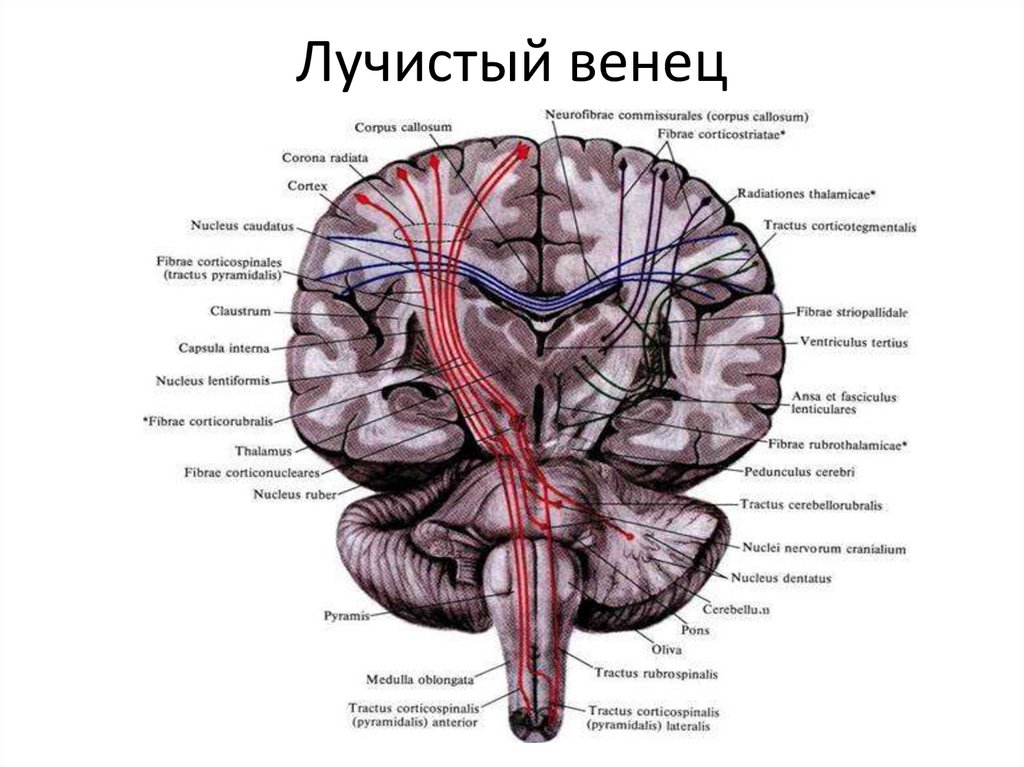

Пирамидная симптоматика в неврологии: ключевые аспекты